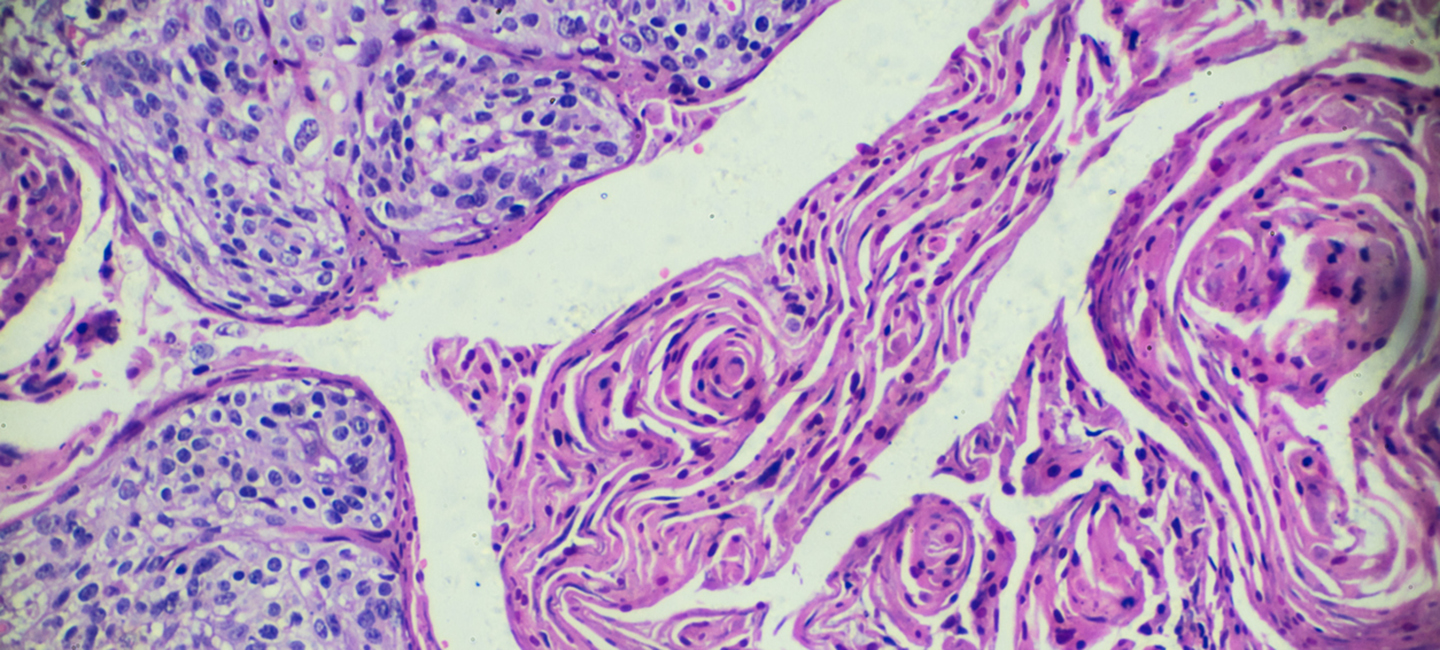

Heading up this clinical trial is Dr. Kamran Ahmed, an assistant member in Moffitt’s Department of Radiation Oncology and a member of Moffitt’s Immunology Program. He explained that immunotherapy is now a cornerstone in the management of many different types of cancer including certain types of cervical cancer. “Studies have revealed that radiation therapy can improve the response rates for immunotherapy,” added Ahmed. “This novel trial at Moffitt studies the use of focused, high dose radiation therapy with the immunotherapy, atezolizumab, to see whether radiation can improve the response rate to immunotherapy and ultimately improve treatment outcomes for metastatic, recurrent, or persistent cervical cancer.”